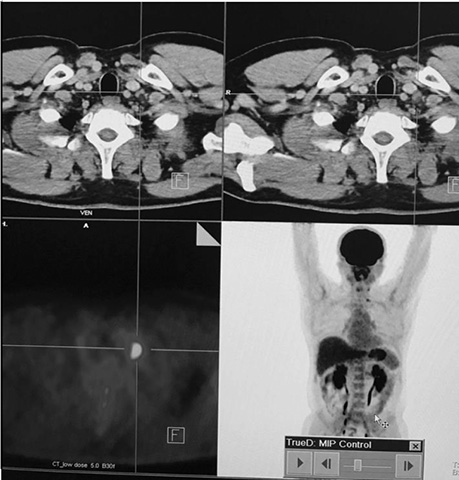

У пацієнта Б. з фолікулярною формою ДРЩЗ на постлікувальному скані після 5 курсу РЙТ відмічалася відсутність накопичення 131I-NaI. При цьому за даними КТ та високими показниками ТГ можна було передбачити можливість метастазування. Хворому рекомендовано ПЕТ / КТ з 18F-ФДГ (рис. 7).

Рис. 7. ПЕТ / КТ з 18F-ФДГ. Візуалізується вогнище в лівій легені

На КТ-зображенні відмічається чітке вогнище в лівій легені, яке збігається при накладанні метаболічного ПЕТ-скану. Інші дрібні вогнища відповідають фіброзним та кальцинатним утворенням.

Отже, на етапі одержання структурного зображення вже була отримана інформація про наявність метастатичного вогнища в легені, яка була підтверджена за допомогою 3D-трансформації (рис. 8).

Рис. 8. Трансформація зображення — метастатичне вогнище в легені

Наступним етапом була таргетна терапія йод-негативного метастатичного вогнища в легені. Для оцінки результативності лікування проведено ПЕТ / КТ з 18F-ФДГ. За даними метаболічного сканування достовірних змін як щодо розмірів вогнища, так і ступеня його функціональної активності не виявлено.